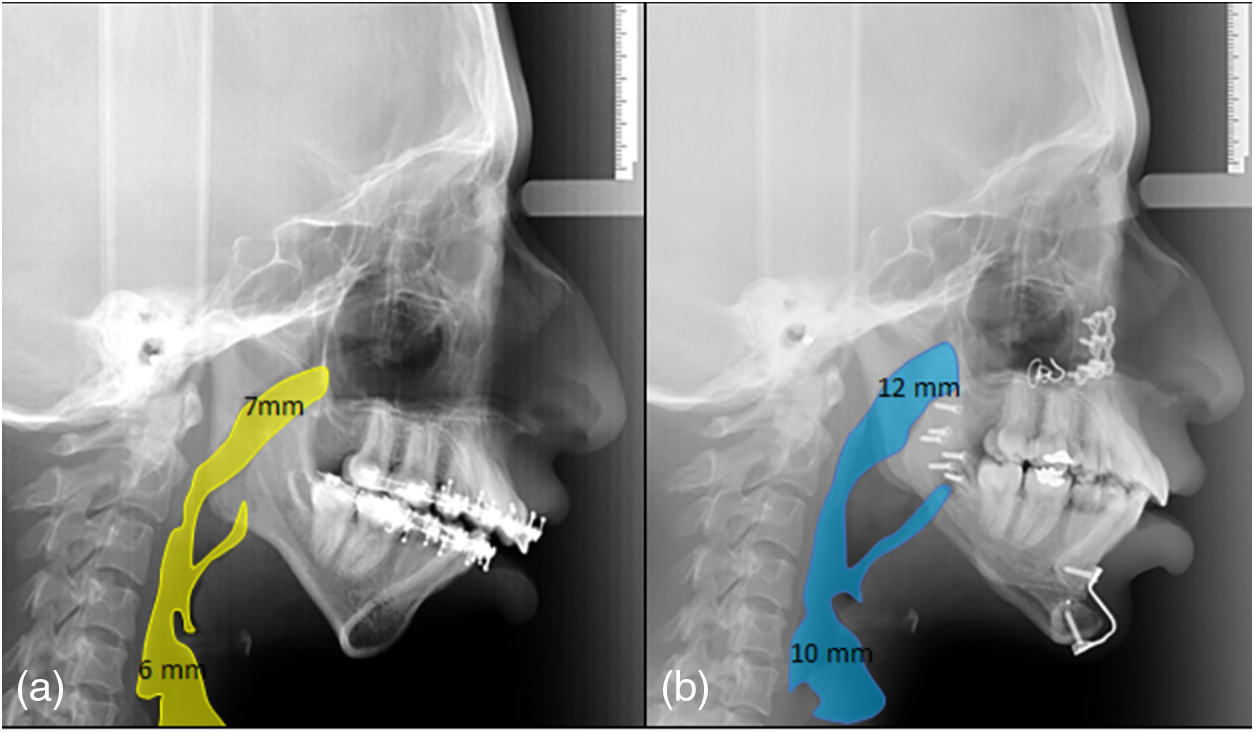

Le Fort I osteotomy: A 5 mm mandibular intrusion was performed with a mandibular response. Surgical planning was performed considering a previous cephalometric prediction and performing the procedure (Figs. 2a, 2b).

OSRAM: This surgical procedure was performed to advance the mandible by 7 mm and to rotate the body of the mandible in a counterclockwise direction, with an open posterior bite of 3 mm to achieve a greater projection of the chin (Fig. 3c).

Fig. 3. Cephalometric prediction: a) Le Fort I maxillary osteotomy for anterior intrusion and mandibular response, b) OSRAM for advancement and counterclockwise rotation of the mandibular body.

A mentoplasty was performed to achieve a 6 mm advancement of the mandible (Fig. 3d).

The clinical triad observed in 80% of SMG patients and consanguinity in this case support the diagnosis of this rare autosomal recessive disorder [3]–[5]. A multidisciplinary team including genetics, craniofacial surgery, gastroenterology, nutrition, neurology, otolaryngology, phonology, pediatric dentistry, maxillofacial surgery and orthodontics was formed to treat this patient. In the case of orthodontics and maxillofacial surgery, the goals were focused on improving function and aesthetics. The severe transverse collapse was solved. The airway was improved by palatal expansion. To achieve better and more predictable results, preoperative cephalometric planning was performed (Fig. 2). Preoperative decompensation was achieved using an articulating device (Fig. 6). Furthermore, the facial profile was improved using advanced mentoplasty (Figs. 5, 7). Changes in preoperative and postoperative cephalometric measurements are shown in Table II. Significant results were achieved at both the facial and the skeletal levels. The ameloplasty and the bite adjustment provided a canine guide and functional incisors that helped open the airway (Fig. 8). Our results reflect the efficacy of orthodontic treatment and surgical procedures in improving the function and aesthetic appearance of the patient. The need for continued research in this area to improve the understanding and clinical management of this unique population is highlighted by the lack of data on the prevalence of dentofacial disease in patients with GMS [5]. This case report is consistent with those reported in other articles showing the clinical trial of GMS, evidenced by facial and dental features such as mandibular retrognathism, deep palate, dental malocclusion, and dental fusion [10]–[12].